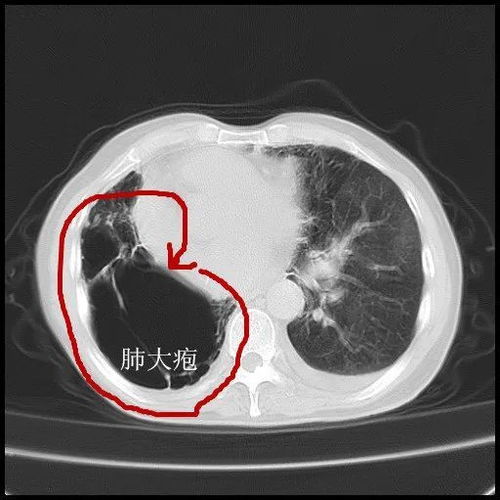

要看嚴重度。無癥狀的肺大皰不需治療,一般是加強營養(yǎng)、多運動、休息好保持心情舒暢、避免寒冷刺激,當然如果肺大炮較多且較大,則避免用力吹氣,比如不做肺功能檢查,避免肺部感染。伴有慢性支氣管炎或肺氣腫的患者,主要治療原發(fā)病變.繼發(fā)感染時,應用抗生素.肺大皰體積大,占據(jù)一側胸腔70%~100%,臨床上有癥狀,而肺部無其它病變的患者,手術切除肺大皰可以使受壓肺組織復張,呼吸面積增加,肺內分流消失,動脈血氧分壓提高,氣道阻力減低,通氣量增加,患者胸悶,氣短等呼吸困難癥狀可以改善.